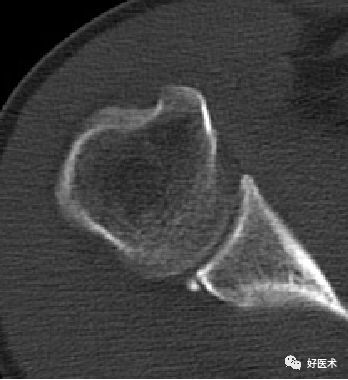

五、CT检查

能很好地观察关节的稳定性、骨皮质连续性,可以观察不易发现的关节内骨片

-

准确评估骨性Bankart病变、Hill-sachs病变

CT显示肩关节不稳

后脱位:反Hill-Sachs损伤

后关节盂撕脱小骨折

若盂唇损伤合并关节盂骨质损伤,称为骨性Bankart病变

骨性Bankart病变